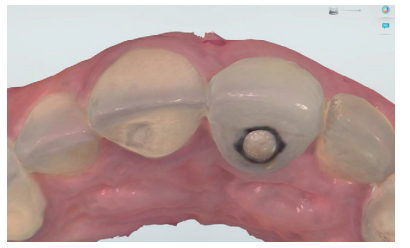

Tras conseguir un volumen de tejido óptimo mediante el manejo del provisional (Figura 17), se realizó un primer escaneado del maxilar con la corona provisional atornillada para obtener la anatomía (Figura 18) y, posteriormente, un segundo escaneado sin la misma, registrando de forma precisa los contornos gingivales y el perfil de emergencia conseguido (Figura 19), así como la posición del implante mediante el scan body (Figuras 20 y 21). Para un correcto duplicado del perfil de emergencia, se procedió a escanear la corona provisional fuera de la boca (Figuras 22 y 23), evitando tener que realizar la técnica clásica de un transfer individualizado17. Estos registros fueron enviados al laboratorio protésico, el cual diseñó una estructura metálica sinterizada postmecanizada (Figura 24). Una vez realizada de forma satisfactoria la prueba de la estructura (Figura 25), se tomó el color de la restauración (A2 guía VITA) mediante un filtro de luz polarizada (Figura 26). Estos registros se enviaron de nuevo al laboratorio protésico para la finalización de la corona implantorretenida sobre los modelos impresos (Figuras 27 y 28). Previo a la colocación de la corona definitiva, se comparó el perfil de emergencia de la corona provisional con la definitiva, viendo la similitud entre ellas (Figura 29), consiguiendo así preservar los perfiles mantenidos desde el día de inicio del tratamiento.